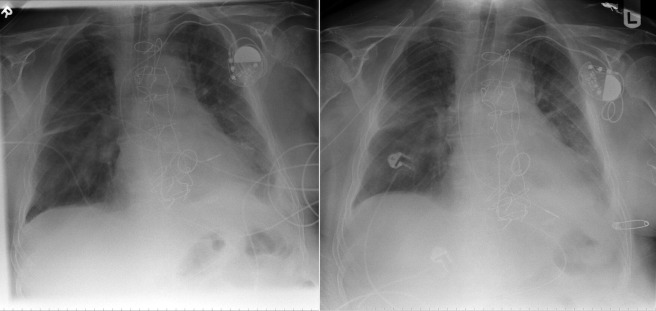

Chest radiography has a standard role in the identification of several potential complications such as pneumothorax, hemothorax, and several forms of malposition after insertion of pacemakers, implantable cardioverter defibrillators (ICDs), and cardiac resynchronization therapy devices.

Pacemaker leads are apparent, and ICDs are more obvious because of their larger coils. Coronary sinus leads for cardiac resynchronization therapy are finer leads.

Endocardial Pacer Leads

The position and integrity of endocardial pacer leads should be verified, especially when pacemaker dysfunction is clinically suspected ( Graphics 23-1 to 23-4 ; Figs. 23-1 to 23-15 ).The most common cause of pacemaker dysfunction that is apparent on the chest radiography is distal lead displacement/misplacement.